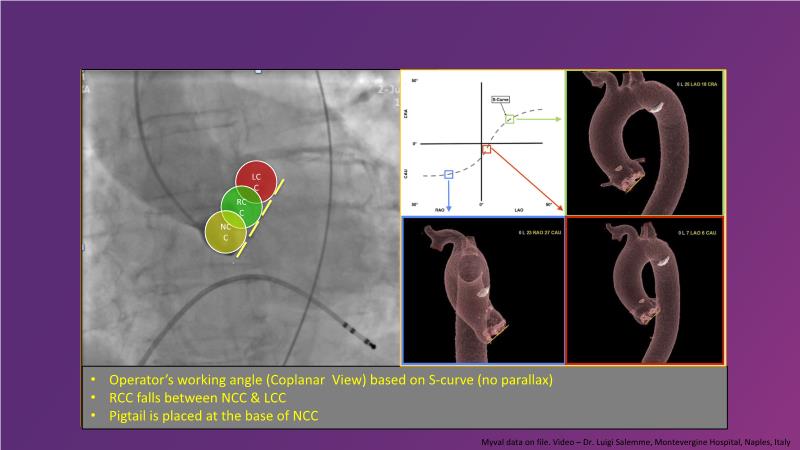

Join this session for an update on the science and clinical advancements in next-generation balloon-expandable transcatheter aortic valve replacement (TAVR) and thin strut bioresorbable scaffolds (BRS). Discover how these innovative technologies can improve clinical outcomes by exploring case-based challenging scenarios and learn effective strategies for tackling them.

- To highlight next generation transcatheter heart valve technologies that can contribute to better clinical outcomes

- To discuss case-based challenging scenarios and how to tackle them